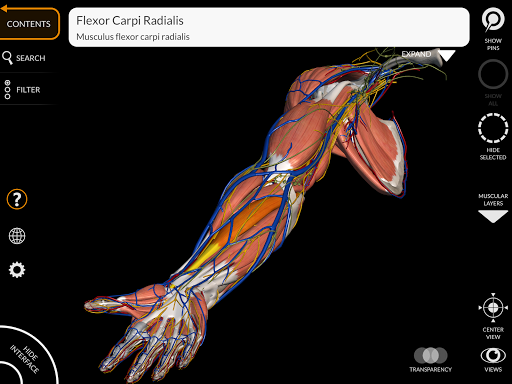

"Anatomía - Atlas 3D" permite estudiar la anatomía humana de forma fácil e interactiva.

A través de una interfaz sencilla e intuitiva es posible observar cada estructura anatómica desde cualquier ángulo.

Los modelos anatómicos 3D son especialmente detallados y con texturas de hasta una resolución de 4k.

La subdivisión por regiones y las vistas predefinidas facilitan la observación y el estudio de partes individuales o grupos de sistemas y las relaciones entre los diferentes órganos.

nervioso • Sistema respiratorio • Sistema digestivo • Sistema urogenital (masculino y femenino) • Sistema endocrino • Sistema linfático • Sistema ocular y auditivo CARACTERÍSTICAS • Interfaz sencilla e intuitiva • Rotar y hacer zoom en cada modelo en el espacio 3D • Opción para ocultar o aislar uno o varios modelos seleccionados • Filtro para ocultar o mostrar cada sistema • Función de búsqueda para encontrar fácilmente cada parte anatómica • Función de marcador para guardar vistas personalizadas • Rotación inteligente que mueve el centro de rotación automáticamente • Función de transparencia • Visualización de músculos a través de niveles de capas desde las superficiales hasta las más profundas • Al seleccionar un modelo o un pin, aparece el término anatómico relacionado • Descripción de los músculos: origen, inserción, inervación y acción • Mostrar/ocultar interfaz de usuario (muy útil con pantallas pequeñas) MULTILINGÜE • Los términos anatómicos y la interfaz de usuario están disponibles en 11 idiomas: latín, inglés, francés, alemán, italiano, portugués, turco, ruso, español, Chino, japonés y coreano • Los términos anatómicos se pueden mostrar en dos idiomas simultáneamente REQUISITOS DEL SISTEMA • Android 8.0 o posterior, dispositivos con al menos 3 GB de RAM Reversi